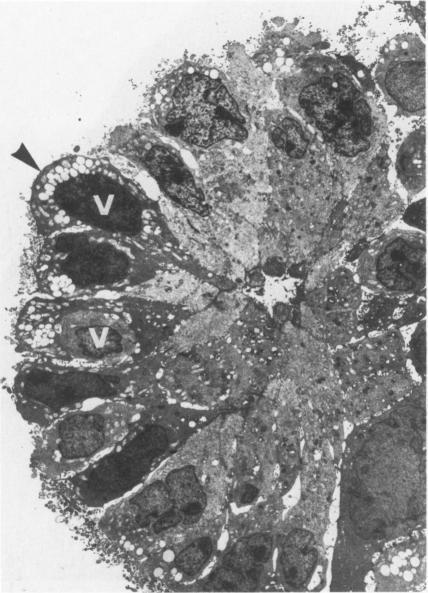

The presence of an unusual cell type in two human colon carcinoma cell lines is reported. The cells show the same morphology as "tuft" (caveolated) cells present in normal gastrointestinal epithelium. Tuft cells were seen in cell line LIM 1863 growing in vitro and in human colon carcinoma cell line LIM 2210 growing as subcutaneous solid tumour xenografts in nude mice. Characteristic morphologic features of tuft cells included a wide base, narrow apex and a tuft of long microvilli projecting from the apical surface. The microvilli are attached by a core of long microfilaments passing deep into the apical cytoplasm. Between the microvilli are parallel arrays of vesicles (caveoli) containing flocculent material. Two different but not mutually exclusive explanations for the presence of tuft cells are proposed. The first explanation is that tuft cells came from the resected tumour and have survived by mitotic division during subsequent passages. The second explanation suggests that tuft cells are the progeny of undifferentiated tumour cells. Descriptions of tuft cells in colon carcinomas are uncommon and possible reasons for this are presented. The morphology of tuft cells is consistent with that of a highly differentiated cell specialised for absorption, and these new models provide an opportunity to further investigate the structure and function of tuft cells.